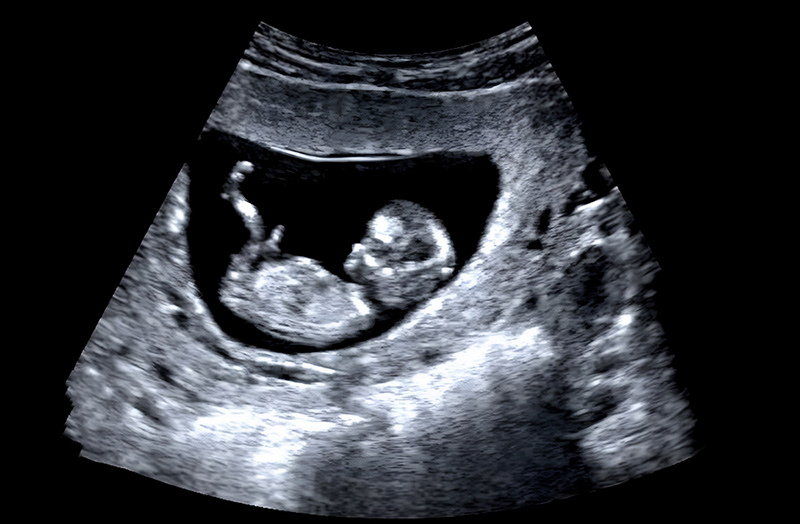

ลูกดิ้นแค่ไหนถึงเรียกว่าปกติ ? ชวนคุณแม่ตั้งครรภ์มาเช็กพัฒนาการลูกดิ้นในแต่ละไตรมาส พร้อมสอนวิธีนับและวิธีกระตุ้นให้ลูกดิ้นเพื่อความปลอดภัยของทารกในครรภ์

ช่วงเวลาที่ตื่นเต้นที่สุดช่วงหนึ่งของการตั้งครรภ์ก็คือตอนที่เราสัมผัสได้ว่าเจ้าตัวเล็กในท้องเริ่มขยับตัวนั่นเองค่ะ แต่นอกจากความดีใจแล้ว เชื่อว่าคุณแม่หลายคนคงมีความกังวลตามมาว่า แล้วแบบนี้ลูกดิ้นแรงไปไหม ? หรือวันนี้ทำไมเงียบจัง ? คำถามที่พบบ่อยที่สุดคือ ลูกดิ้นแค่ไหนถึงเรียกว่าปกติ กระปุกดอทคอมจึงพาไปไขข้อสงสัยเรื่องทารกในครรภ์ พร้อมวิธีกระตุ้นให้ลูกดิ้นกันค่ะ

โดยปกติแล้ว ทารก จะเริ่มขยับตัวตั้งแต่อยู่ในท้องได้ประมาณ 7-8 สัปดาห์แล้วค่ะ แต่ขนาดตัวเขายังเล็กมากจนคุณแม่ยังไม่รู้สึก